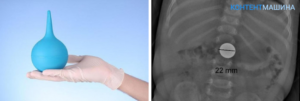

Пример рентгена инородного тела

Как выяснить, какой предмет проглочен

Если родители узнают или подозревают, что малыш проглотил объект небольшого размера, врачи проводят рентгенографическое исследование пищевода, желудка и брюшной полости. Этот метод подходит лишь для выявления металлических предметов. Если в результате рентгена не обнаруживается инородных тел в пищеводе или желудке, но есть симптомы, указывающие на их наличие, то назначается эндоскопия.